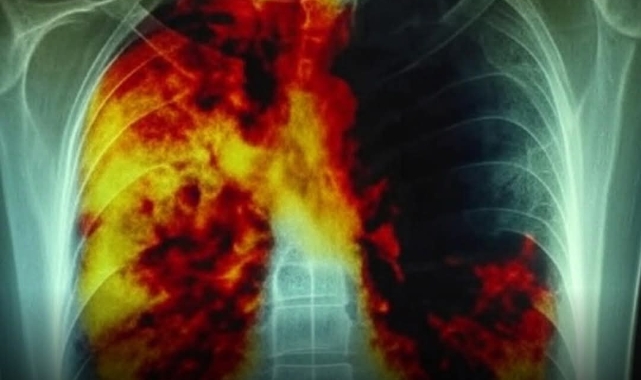

Dünyanın İlk Akciğer Kanseri Aşısı 7 Ülkede Klinik Deneylerde

Kanserle mücadelede çığır açacak bir gelişme yaşandı. Dünyanın ilk akciğer kanseri aşısı, yedi ülkede klinik deneylere başladı. Bu tarihi adım, en ölümcül hastalıklardan biri olan akciğer kanserinden etkilenen milyonlarca insana umut veriyor.

Aşı, sadece mevcut tümörleri tedavi etmeyi değil; aynı zamanda akciğer kanserinin gelişimini potansiyel olarak önlemeyi hedefliyor. Bu yönüyle tıp dünyasında devrim niteliğinde bir ilerleme olarak değerlendiriliyor.Akciğer kanseri, dünya genelinde en fazla can kaybına yol açan kanser türü olarak biliniyor. Bugüne kadar kemoterapi, radyasyon ve cerrahi yöntemler başlıca tedavi seçenekleri arasında yer aldı. Ancak bu yöntemler çoğunlukla ağır yan etkiler ve sınırlı başarı oranları ile sonuçlanıyordu. Uzun yıllardır hayal edilen “bağışıklık sistemini kanser hücrelerini tanıyıp yok etmeye eğitebilecek bir aşı” fikri, artık gerçek olma yolunda.Klinik deneyler kapsamında, aşının tümörleri küçültme, nüksetmeyi önleme ve hayatta kalma oranlarını artırma potansiyeli incelenecek. İlk çalışmalar, aşının katılımcılarda güçlü bir bağışıklık yanıtı oluşturduğunu ortaya koydu.Uzmanlara göre, eğer bu aşı başarıya ulaşırsa, kanser tedavisinde yaklaşımı “reaksiyondan önlemeye” kaydırarak büyük bir paradigma değişimine yol açabilir. Ayrıca bu gelişme, gelecekte diğer kanser türlerine yönelik aşıların geliştirilmesinin de önünü açabilir.